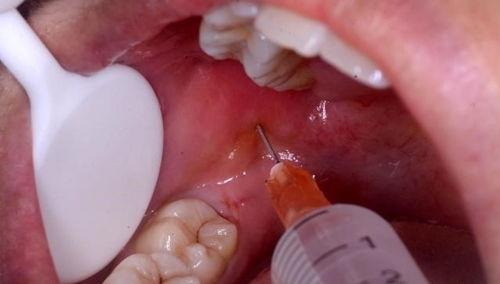

当你走进手术室,你会看到医生们忙碌的身影。他们穿着白大褂,戴着口罩,全神贯注地操作着。这时候,你可能会好奇,他们到底是怎么拔掉智齿的?

别急,让我带你一探究竟。在拔智齿的视频中,你可以看到医生们是如何使用专业的工具,小心翼翼地分离智齿与牙槽骨的连接。他们会用牙挺、牙钳等工具,将智齿从牙槽骨中拔出。整个过程看似简单,但实际上需要医生们丰富的经验和精湛的技艺。